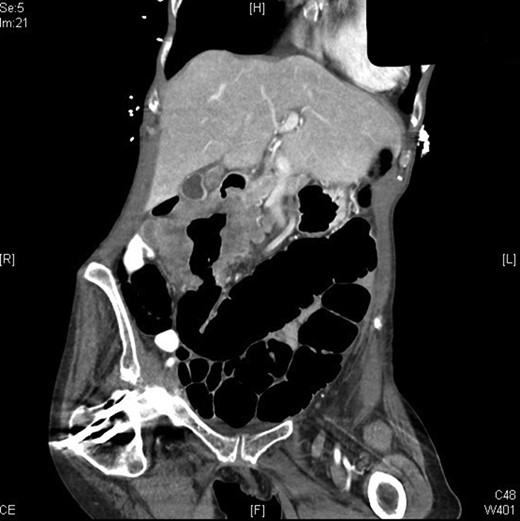

A 70-year-old female presented to the emergency department with complaints of diarrhea, vague, dull abdominal pain, unintentional weight loss and poor appetite. No hematochezia or melaena stated. Fecal occult is strongly positive in the ED. No endoscopies were found in her records. PMHx included COPD, osteoarthritis and DVT. Significant physical exam findings included mild, diffuse abdominal tenderness and RUQ palpable mass, and normal bowel sounds. Labs were significant for a hemoglobin of 5.7, hematocrit of 18.6% and CEA of 29.6. An abdominal/pelvis CT exhibited a 6 cm circumferential mass of the hepatic flexure (Figs 1–3). Two days later, a right hemicolectomy with en bloc pancreaticoduodenectomy was performed. Pathology showed adenocarcinoma stage IIIc (Figs 4–10). Post-operatively, an abdominal/pelvis CT showed bilateral pulmonary emboli and a 14 cm pelvic abscess. Bilateral lower extremity ultrasound showed low probability for DVT. Exploratory laparotomy was performed where the pelvic abscess was seen and extensive lysis of adhesions, resection of ileocolonic anastomosis for contained leak and ileostomy performed. Approximately 4 months after discharge, the patient passed away while in a long-term care facility.

A 2013 study showed that patients who are appropriate for right hemicolectomy with en bloc pancreaticoduodenectomy have the following characteristics: ‘(i) no distant metastasis, (ii) R0 resection being possible on the basis of the preoperative examination, (iii) the patient’s condition being good enough to accept radical multivisceral resection and (iv) the surgical team being experienced enough to perform the procedure’ [10]. Preoperative evaluations are strongly recommended to ensure that patients qualify. Preoperative staging is also a key factor; this is done through abdominal CT scans. CT scans have a significant (99%) ability to detect liver metastases, moderate ability to reveal cT4 stage (86%) cancers but are poor at detecting peritoneal carcinomatosis [10]. CTs are able to distinguish colonic tumor stages pre-operatively and can show invasion through the muscularis propria, indicating stage T3/T4 [10].